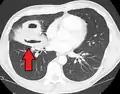

![]() | |

| Computed tomography (CT) scan of chest showing bilateral pneumonia with abscesses, effusions, and caverns. 37-year-old male. | |